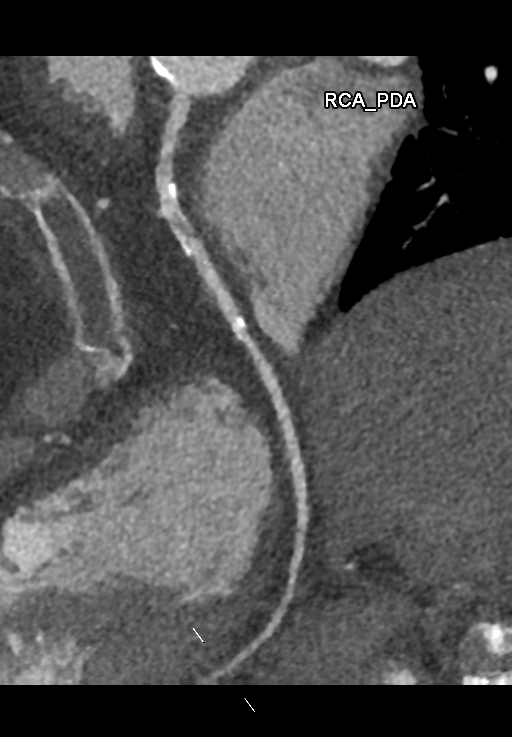

A 78-year-old woman with hypertension, hyperlipidemia, and a history of PCI to the right coronary artery with bare-metal stent placement in 2001 presented with a one-month history of stable angina. She underwent CT coronary angiography, which demonstrated moderate to severe in-stent restenosis in the RCA. She was admitted electively for coronary angiography and possible PCI. Physical examination was unremarkable, with no murmurs or signs of heart failure.

Dominance: Right Left Main: No significant stenosis LAD: Mild distal disease LCx: Minor disease RCA: 80% in-stent restenosis at proximal segment; 80% calcified de novo stenosis at mid to distal RCA

The diagnostic angiogram confirmed significant ISR at the proximal RCA stent, with severe calcification, and a de novo significant stenosis in the mid-distal RCA. The procedure was performed via the right radial artery approach. Initial attempts to engage the RCA with a 6Fr Ikari Left 3.5 guide were unsuccessful. Switching to a 6Fr Judkins Right 4 guide provided suboptimal support, necessitating the use of a Guidezilla II guide extension catheter. The posterior descending artery (PDA) was wired with a Sion Blue wire. Intravascular ultrasound (IVUS) confirmed severe calcification within the ISR segment. Predilatation of the distal RCA lesion and proximal RCA ISR with an Aperta NSE 3.0/13 balloon resulted in poor balloon expansion. Intravascular lithotripsy (IVL) was performed using a 3.0/12Shockwave balloon, delivering 100 cycles to both lesions. Post-IVL IVUS demonstrated adequate lesion preparation. The distal RCA lesion was stented with an Ultimaster Nagomi 3.0/28 mm DES, followed by post-dilation with a non-compliant 3.25/15 mm balloon.The proximal RCA ISR was treated with an Ultimaster Nagomi 3.5/33 mm DES, post-dilated with a non-compliant 3.5/15 mm balloon up to 22atm. Final IVUS confirmed good stent expansion and apposition, with no edge dissection. The final angiogram demonstrated a satisfactory result with TIMI 3 flow.